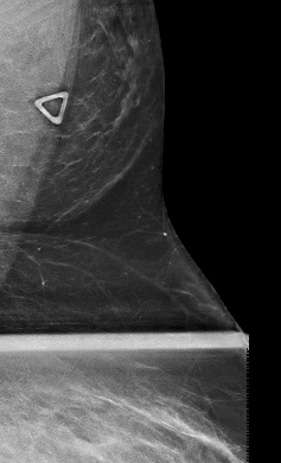

On mammography, accessory breast tissue in the axilla presents as variable quantities of fibroglandular densities scattered amongst fat, which is separate from the main pectoral breast tissue2 (Fig. 1). This appearance should be distinguished from the axillary tail of Spence, which is fibroglandular tissue that is contiguous with the main duct system of the breast tissue and extends into the axilla.1 Of note, if a focal asymmetry in the axilla is new, changed, or identified on a baseline study, a diagnostic exam should be performed to rule out a pathologic process.2